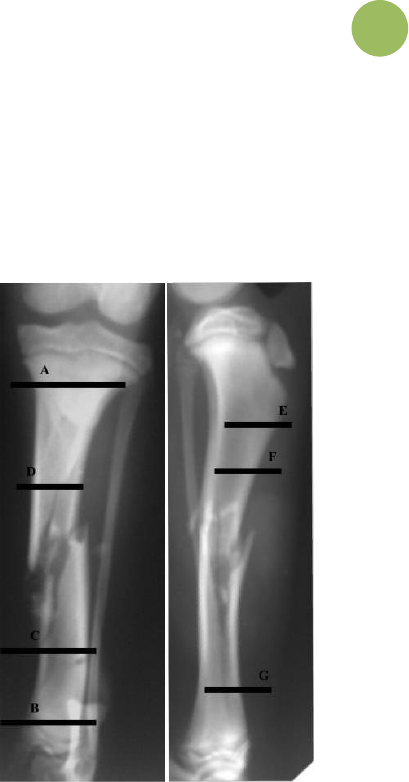

18 - Considere a fratura abaixo, em que se decidiu pelo tratamento com um

fixador externo linear do tipo 1B, com 2 pinos em cada plano no

fragmento proximal e 2 pinos no plano medial e 1 crânio medial no

fragmento distal. Assinale a alternativa que dispõe a ordem correta de

aplicação de cada um dos pinos de Schanz:

a) A–B–C–D–E–F–G.

b) A–B–D–C–E–G–F.

c) B–E–D–A–C–F–G.

d) A–E–B–G–F–D–C.

e) D–C–F–A–B–G–E.